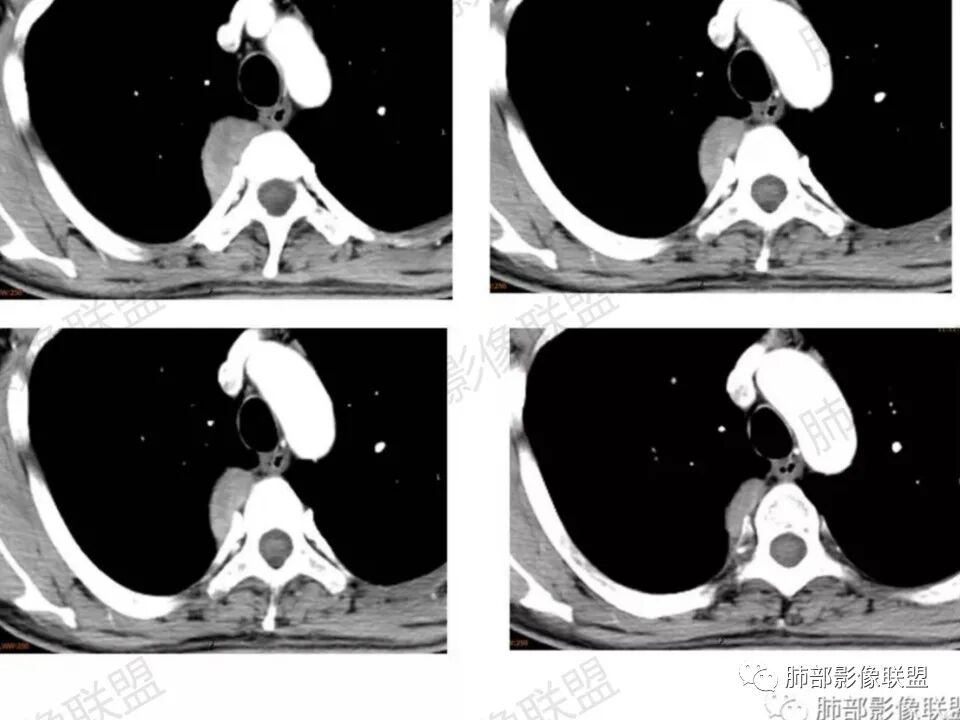

男,45岁,反复背痛3年;病程长,发展缓慢;后纵膈,与脊柱关系说不清;强化明显,有分区;诊断:神经源肿瘤;良性鉴别:间质来源肿瘤。

右侧后纵隔肿块,宽基地附着与胸膜,可见胸膜尾征,与肺组织交界清晰,没有平扫,增强后不均匀明显强化,部分可见向椎孔延伸,综合考虑:神经源性肿瘤(神经鞘瘤,神经节细胞瘤),鉴别孤立性纤维瘤

后纵膈肿块,边界清晰,增强后呈不均匀明显强化,渐进性强化,并向椎间孔延伸,首先考虑良性,神经源性肿瘤,神经鞘瘤可能

右后纵膈肿块,脊柱旁,邻近椎间孔扩大向内延伸,密度不均匀,强化明显,考虑神经源性肿瘤,鞘瘤可能性大。

中年男,慢性病程,右后上纵隔脊柱旁肿物,呈D字型凸向肺部,见胸膜尾,定位肺外;肿物不规则强化,近脊柱边缘部分清晰可见脂肪间隙,部分与脊柱相连包绕,未见骨破坏,上方似延伸至颈部。定性良性,孤立性纤维瘤可能性大,鉴别神经鞘瘤。

患者中年男性,反复背部疼痛3年。胸部CT:右后纵隔、胸膜下紧贴脊柱软组织肿块,边缘清晰光滑,长袖与脊柱平行,增强轻度强化,内见低密度坏死区。定位肺外,定性良性,综合考虑神经源性肿瘤,神经鞘瘤可能性大,神经节细胞瘤及其他待排。

后纵隔脊柱旁占位,病灶内有低密度区,增强扫描不均匀强化,失状位似沿神经走形,部分进入锥间孔,首先考虑神经源性肿瘤。

患者,男性 45岁,反复背部疼痛3年。右侧后纵膈脊柱旁软组织影,匍匐样生长,临近骨质未见破坏征象,软组织局限性隆起,椎间孔未见明确扩大。增强呈渐进性升高,内部强化不均匀,未见坏死、囊变。结合病史,总体考虑良性病变,神经来源,神经鞘瘤可能。

男45岁,病史3年。右后纵隔脊柱旁见孤立性肿块影,边界清晰,胸膜被掀起。定位,胸膜外,增强病灶不均匀强化,向椎间孔延伸,考虑神经源性肿瘤,神经鞘瘤。鉴别,神经纤维瘤,SFT

这个病例定位肺外没问题,病灶呈宽基底,见明显的胸膜掀起征,定位胸膜或右后纵隔来源,而且肿块提示肋间动脉穿行,脏层胸膜来源可能性不大(脏层胸膜由肺动脉及支气管动脉供血),那就是壁层胸膜跟纵隔来源,但是图像上有2个层面是胸膜外间隙有受压推移,所以壁层胸膜来源也不考虑;病灶是渐进性强化,常见的就是间叶来源含有梭形细胞的软组织肿瘤跟后纵隔常见的神经源性肿瘤鉴别,那如何在后纵隔的大山里拨开云雾找到我们想要的答案呢?那小编在这里先理出几个问题: